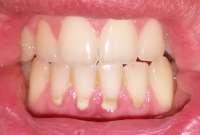

14730060113960.jpg (1696Кб, 3584x2016)

14730060114311.jpg (1712Кб, 3584x2016)

14730060114662.jpg (1558Кб, 3584x2016)

Мои зубки. Запломбировал все дырки коих было много, но внешний вид всё равно оставлял желать лучшего, на последнем приёме у стоматолога спросил насчет отбеливания зубов, какие есть варианты и т.д. она мне ответила, что у меня и так фиговая эмаль и мне нельзя делать отбеливание, дальнейшие расспросы особых результатов не дали. Собственно вопрос - и вправду нет адекватного способа отбелить зубы без вреда для самих зубов? Не очень то хочется бегать желторотиком всю жизнь. И какие еще могут быть способы привести зубы в более привлекательный вид?

>>513114

На чистке зубов был? Что то у тебя между зубов какие то отложения. Или это еда?